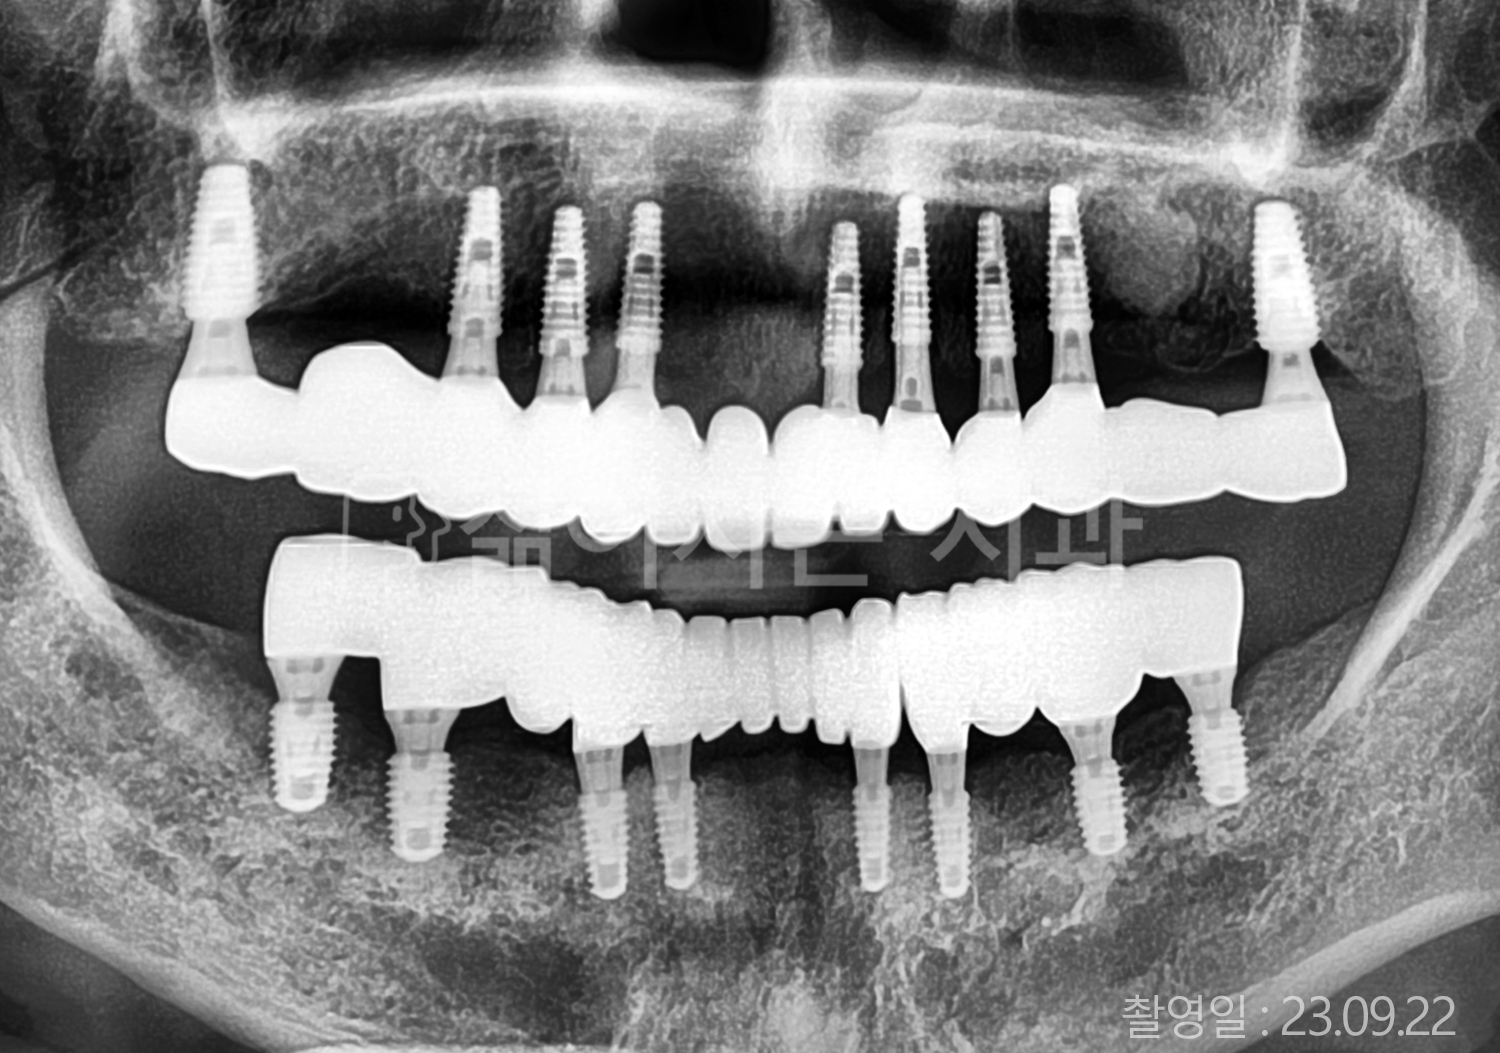

• 80대 전체치아 10개 이상 임플란트

• 60대 고혈압, 당뇨, 고지혈증 전체치아 10개 이상 임플란트

• 60대 전체치아 10개 이상 임플란트

• 60대 고혈압, 고지혈증 전체치아 10개 이상 임플란트

• 50대 고혈압, 당뇨, 고지혈증 전체치아 10개 이상 임플란트

• 70대 골다골증, 파킨스병 전체치아 10개 이상 임플란트

• 40대 전체치아 10개 이상 임플란트

• 60대 골다골증 전체치아 10개 이상 임플란트

• 40대 고혈압 전체치아 10개 이상 임플란트

• 50대 전체치아 10개 이상 임플란트

• 70대 전체치아 10개 이상 임플란트